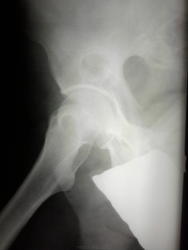

Двухсторонние литические очаги, с четкими, местами склерозироваными контурами. Старый консолидированый перелом левой бедренной кости, после металлоостеосинтеза металлической пластиной. Миеломная или мтс проявили бы себя более агрессивной деструкцией.

tatyana, Вам "зачет"! Здесь действительнро болезнь Реклингхаузена. Наблюдаю данного пациента лет 7. За это время его патологический перелом левой бедренной кости так и не срастается, приобретая все более атрофичный вид в виде перетяжки на уровне излома, потому и держат с металлом до сих пор. Классическая "пастушья палка". Справа в теле подвздошной кости и (менее выраженно) ближе к задней нижней ости, а также в большом вертеле также имеются литические очаги, относительно стабильные за время наблюдения.

А, раз процесс давний, тогда все стало по местам - смущал остеосклероз. Кстати, деформация в виде "пастушьего посоха" бывает не только при гиперпаратиреозе, но и при других состояниях, болезни Педжета, например.